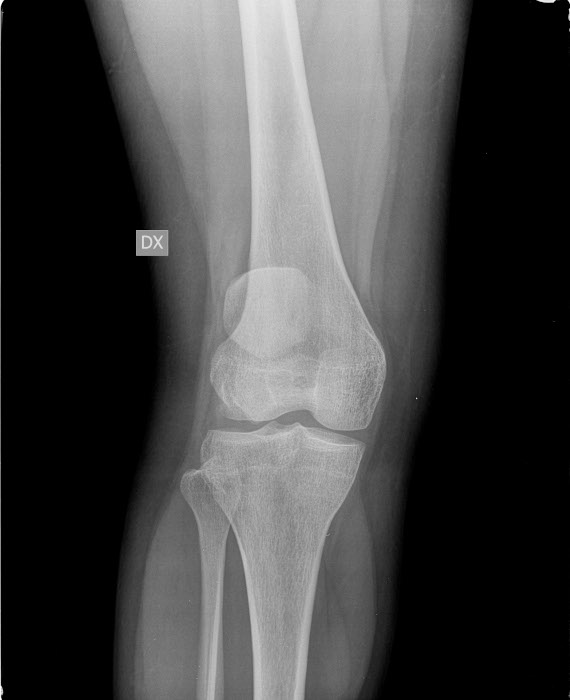

Lussazione della rotula

- Descrizione: Rotula fuori sede rispetto alla troclea femorale, con spostamento laterale, spesso accompagnato da Dolore acuto e gonfiore dell’Articolazione del ginocchio.